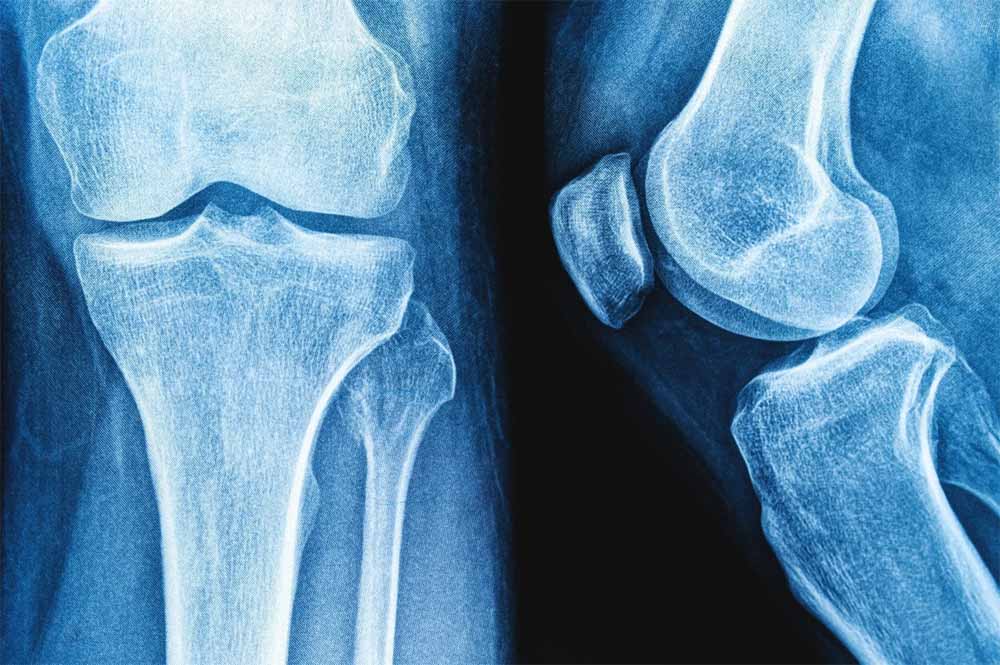

NIT की रिसर्च: हड्डियों की मरम्मत के लिए प्रोटीन से नए उपचार के रास्ते

राष्ट्रीय प्रौद्योगिकी संस्थान (एनआईटी) राउरकेला के शोधकर्ताओं ने मानव शरीर में पाई जाने वाली प्राकृतिक शर्करा जैसे अणु हड्डियों के निर्माण और मरम्मत के लिए जिम्मेदार प्रोटीन, बोन मॉर्फोजेनेटिक प्रोटीन-2 के व्यवहार को कैसे प्रभावित कर सकती है? इसका पता लगाया है।

प्रतिष्ठित पत्रिका बायोकैमिस्ट्री में प्रकाशित इस शोध के निष्कर्षों का उपयोग हड्डी और उपास्थि पुनर्जनन के उन्नत उपचार, बेहतर इम्प्लांट और अधिक प्रभावी प्रोटीन-आधारित दवाओं के विकास में किया जा सकता है। प्रोटीन मनुष्य के शरीर में विभिन्न कार्य करते हैं। टिश्यू के निर्माण और रासायनिक प्रतिक्रियाओं में सहयोग देने से लेकर कोशिकाओं के बीच संकेतों के रूप में कार्य करने तक बड़ी जिम्मेदारी निभाते हैं।

हालांकि सर्वोत्तम उत्पादकता के लिए इनका त्रि-आयामी आकृतियों में सटीक मुड़ना या खुलना आवश्यक है। प्रोटीन क्यों और कैसे खुलते हैं? यह समझना जीव विज्ञान का एक प्रमुख लक्ष्य है। इसका प्रभाव चिकित्सा, जैव प्रौद्योगिकी और ड्रग डिलिवरी पर पड़ता है। इस संदर्भ में हड्डी और उपास्थि के निर्माण, चोटों को ठीक करने और स्टेम कोशिकाओं को अस्थि-निर्माण कोशिकाओं में परिणत करने में बीएमपी-2 महत्वपूर्ण भूमिका निभाता है।